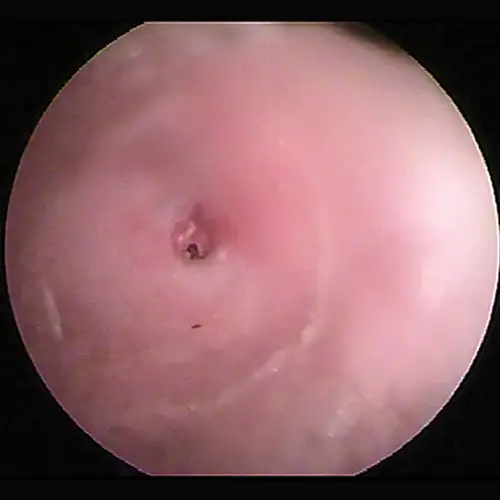

Otoscopic image of domed eardrum with hair and yellow exudate visible in internal ear canal.

FIGURE 16

Bulging eardrum caused by increased fluid pressure in the middle ear

In the Cavalier King Charles spaniel, a condition called primary secretory otitis media can cause bulging of the eardrum resulting from the failure of mucoid drainage from the tympanic bulla through the auditory tube.